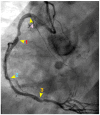

Background: In the study of coronary artery disease, the mechanisms underlying atherosclerosis initiation and progression or regression remain incompletely understood. Our research conceptualized the cardiovascular system as an integrated network of pumps and pipes, advocating for a paradigm shift from static imaging of coronary stenosis to dynamic assessments of coronary flow. Further review of fluid mechanics highlighted the water hammer phenomenon as a compelling analog for processes in coronary arteries. Methods: In this review, the analytical methodology employed a comprehensive, multifaceted approach that incorporated a review of fluid mechanics principles, in vitro acoustic experimentation, frame-by-frame visual angiographic assessments of in vivo coronary flow, and an artificial intelligence (AI) protocol designed to analyze the water hammer phenomenon within an acoustic framework. In the analysis of coronary flow, the angiograms were selected from patients with unstable angina if they had previously undergone one or more coronary angiograms, allowing for a longitudinal comparison of dynamic flow and phenomena. Results: The acoustic investigations pinpointed pockets of contrast concentrations, which might correspond to compression and rarefaction zones. Compression antinodes were correlated to severe stenosis, due to rapid shifts from low-pressure diastolic flow to high-pressure systolic surges, resulting in intimal injury. Rarefaction antinodes were correlated with milder lesions, due to de-escalating transitions from high systolic pressure to lower diastolic pressure. The areas of nodes remained without lesions. Based on the locations of antinodes and nodes, a coronary acoustic action map was constructed, enabling the identification of existing lesions, forecasting the progression of current lesions, and predicting the development of future lesions. Conclusions: The results suggested that intimal injury was likely induced by acoustic retrograde pressure waves from the water hammer phenomenon and developed new lesions at specifically exact locations.